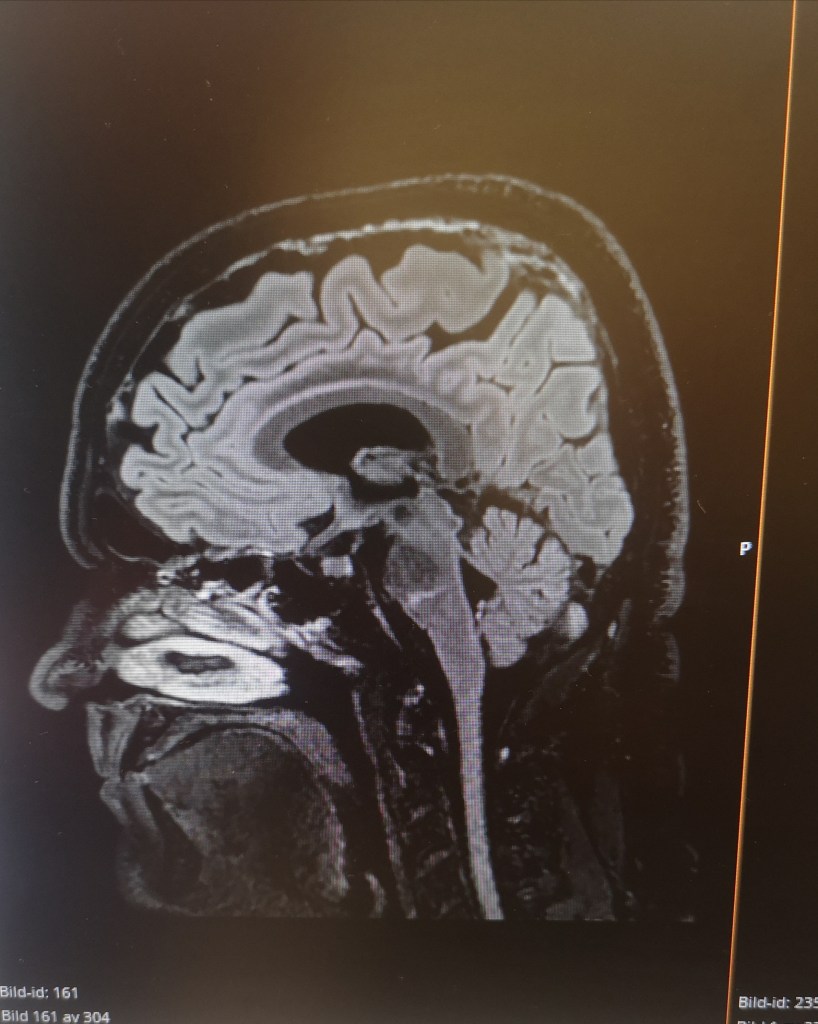

Han sade att jag skulle sluta med protonpumpshämmare (minskar magsyra och blödningsrisk) eftersom mitt immunförsvar sätts ned av det. Magsyran är väldigt viktig för mycket, inte minst för att slå ut olika patogener som man får i sig genom munnen. Risken för blödning i magen med 75 mg trombyl är minimal. Då är det bättre att ta protosonpumpshämmare först vid magkatarrskänsla, inte som förebyggande. Likaså skulle jag sluta med statiner då mina blodkärl var fina på MR. Så det var skönt att fortsättningsvis enbart behöva ta trombyl, som bara motsvarar 1/5 av en magnecyl.